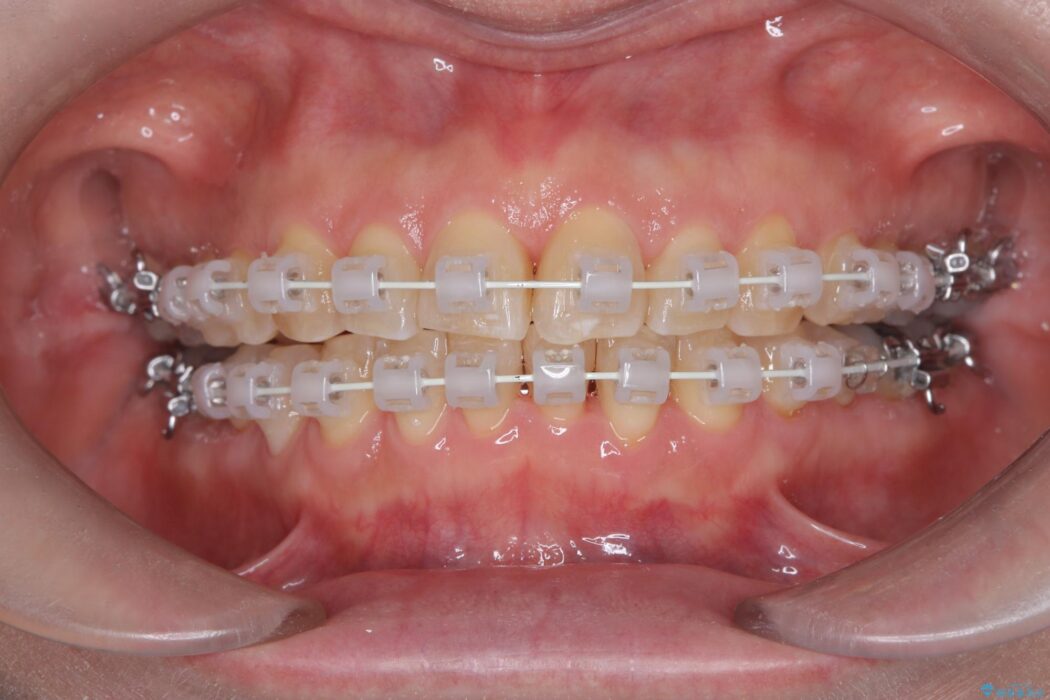

患者様のご希望と状態に合わせ、目立ちにくい審美ワイヤーにて治療を行うこととしました。

スペース確保は、奥歯を少し後ろへ動かす遠心移動と、歯の側面をわずかに削るIPRを併用し、約1年間での治療完了を目指しました。

今回の矯正治療では、歯の色に近い目立たない審美ブラケットとワイヤーを使用しました。